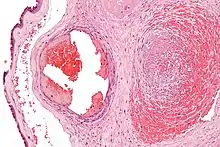

Udsnit af en tilstoppet vene, der viser fibrin (mørkt lyserødt område) omgivet af røde blodlegemer.

Fibrin er et kløvningsprodukt af zymogenet fibrinogen, og dannes ved at serin-proteasen thrombin kløver fire arginin-glycin peptidbindinger i den globulære del af fibrinogen. Herved frigøres 4 små peptider samt fibrin, og sidstnævnte polymeriseres derefter spontant til en fibrinprop. Fibrinproppen, også kendt som en thrombus, stabiliseres derefter af enzymet transglutaminase, der krydsbinder glutamin- og lysinrester i forskellige fibrinmolekyler.